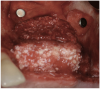

Figure 23  Trephinated core biopsy obtained at 5 months.

Figure 23

Figure 24  Histology: Note active osteocytes with new bone formation.

Figure 24